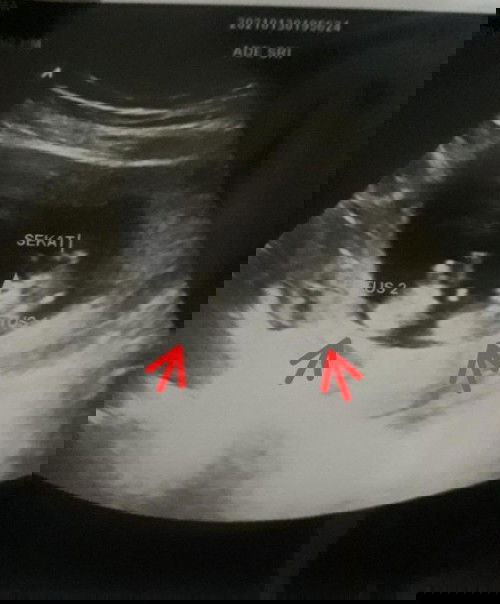

Saya skrg hamil anak kedua...anak pertama skrg 32bulan..memang niat anak umur 2thn kepngn punya baby lagi karna usia juga,skrg saya 31thn..alhamdllah Desember saya telat haid hampir 2minggu pas di check Alhamdulillah positif..periksa ke klinik untuk pastiin memang sudah masuk 7minggu,dan pas cek bulan kedua .baru ketahuan ada 2 calon baby nya,skrg udah masuk 17minggu5hari.. penasaran sama bingung karna saudara dan teman jarang asa yg hamil kembar..buat moms moms yg pernah ha.il kembar juga..bagi bagi sarannya dong??saya smpe skrg kdg2 Masi mual2,dan sering pusing soalnya..beda dengan hamil anak pertama...🙏🙏#seriusnanya #bantusharing #ingintahu #jangandibully